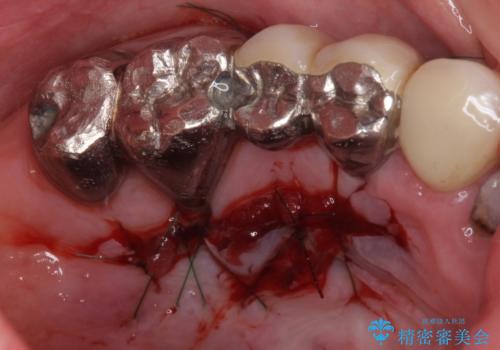

- 咬み合わせにより下の前歯の歯肉が退縮してしまい、根が見えていることが気になるとのことで来院された患者様です。

歯肉退縮に対して、上顎からの結合組織移植術(CTG)により、歯根の被覆を行うとともに、歯肉の厚みを増すことで将来の退縮リスクを抑制することとしました。